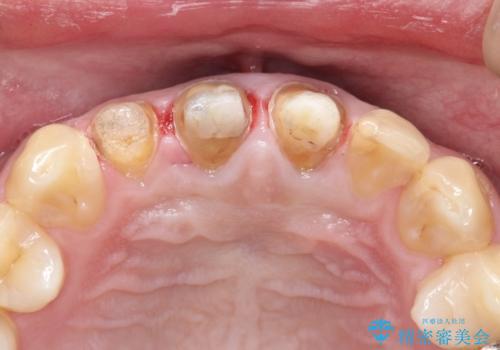

- 前歯のかぶせ物を自然な色味のものにしたいとのことで、来院されました。

保険適用のかぶせ物が装着されており、適合も悪く、変色している状態でした。

土台からの、再治療を行い、オールセラミッククラウンの装着を行う計画としました。